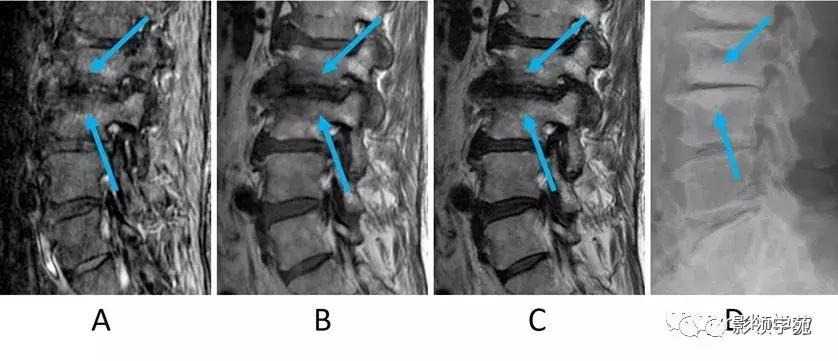

图4:典型的椎间骨软骨病(Modic3型)。男,70多岁。

A:STIR矢状位图像,B:T1WI矢状位图像,C:T2WI矢状位图像,D:侧位X线平片。(A,B,C箭头)可以看到椎间盘间隙变窄,并且在与终板相邻的骨髓中的每个序列上的均呈低信号。平片显示邻近终板的骨硬化(D箭头)。